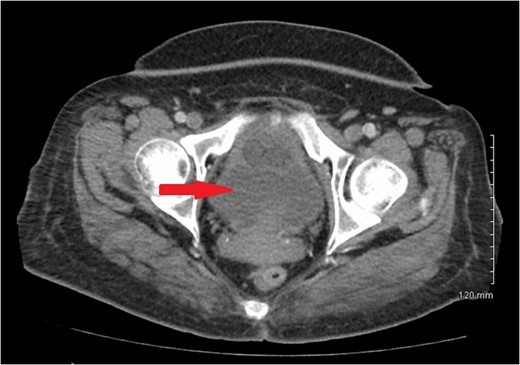

1). There was no evidence of metastatic disease. A 3.8 × 3.3 cm hypodense mass located in the central portion of the uterus was also noted (Fig.

2).

Figure 2:

CT scan of pelvis showing uterine hypodense mass.